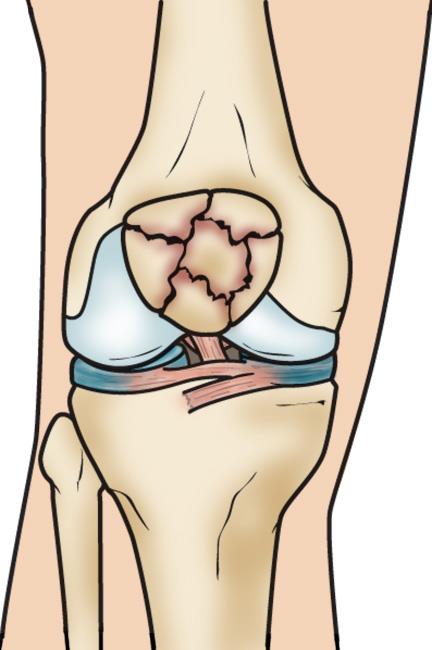

Patellar Fractures (Broken Kneecap

Patellar Fractures (Broken Kneecap

Patella Fracture | Reno Orthopedic Center direct fall on knee cap